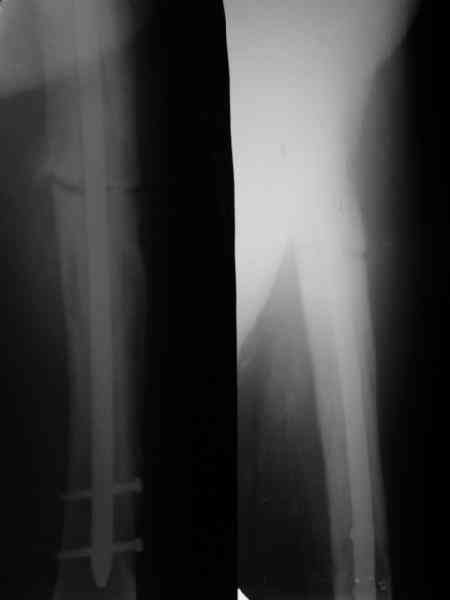

Пациент 82 лет, поступил через 5 мес. с несросшимся переломом после

открытого интрамедуллярного остеосинтеза. Выполнили реостеосинтез

стержнем 12 мм. ( мах. доступного нам в 2003 г.) Через 4 мес

динамизация. В течении 2х лет сращения нет, тем не менее конечность

опорна (ходит с тростью). От очередного реостеосинтеза отказались из-за

сопутств. патологии.